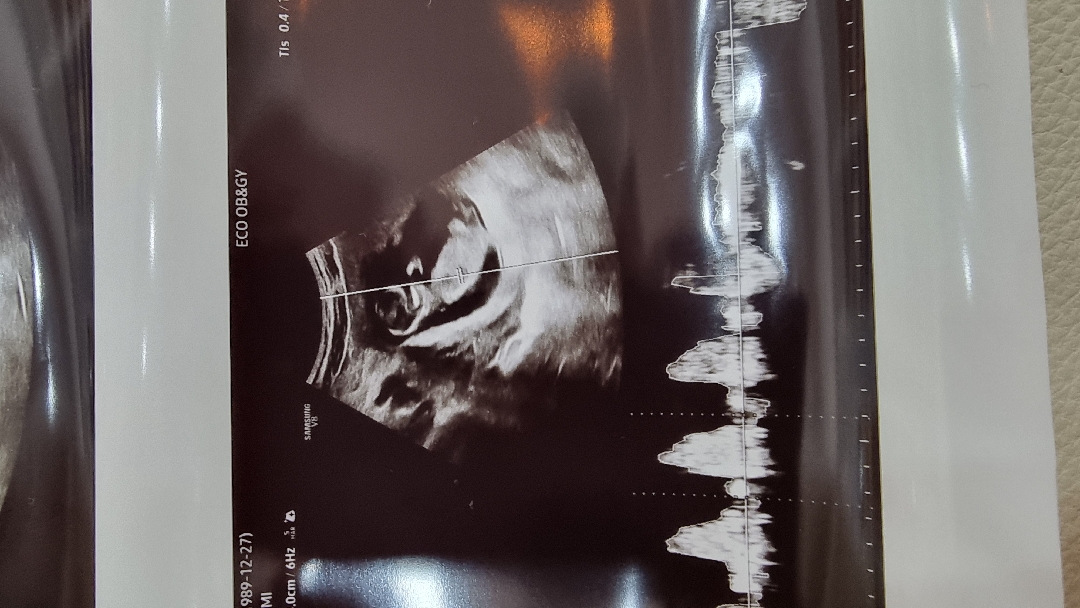

12주 각도법 보이시나요??

넘 궁금하네요!! 오늘 보고왔는데 저는 각도법에 대해 연구를 많이했는데....잘모르겠네요ㅜㅜ 혹시 고수님들 계실까요~??